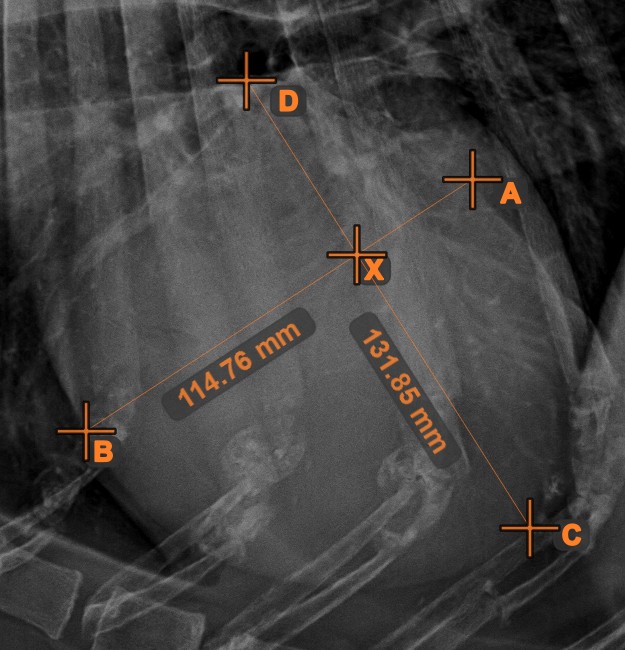

Linienkreuzung¶

Lokalisieren und markieren Sie schnell und präzise den Schnittpunkt zwischen zwei vorhandenen Linien mit dem Werkzeug Linienkreuzung

.

Wählen Sie das Werkzeug aus der linken Symbolleiste aus und weisen Sie es einer der verfügbaren Maustasten zu. Wählen Sie zwei bereits in der Szene gezeichnete Linien aus, um die Messung abzuschließen. Der Schnittpunkt der Linien wird automatisch berechnet und in der Szene markiert. Der Schnittpunkt zweier Linien wird stets mit dem Buchstaben X markiert.

Informationen

Wenn sich zwei Linien nicht direkt schneiden, wird der Schnittpunkt ihrer verlängerten Projektionen in der Szene markiert.